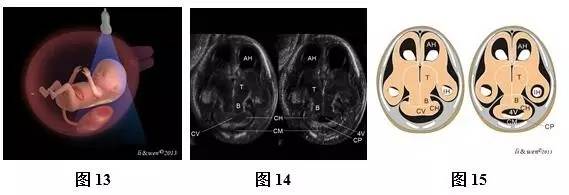

(一)11~13+6孕周正常胎儿颅脑及颜面方法及内容

超声扫查方法:声束平面从胎儿前额进入,通过胎儿侧脑室对胎儿颅脑进行横切面扫查(图10),即可获得侧脑室水平横切面(图11,12);然后声束平面以前额为基点,向胎儿尾侧和前方扫查(图13,16,19,22),依次可获得小脑水平横切面(图14,15)、双眼球冠状切面(图17,18)、鼻后三角冠状切面(图20,21)和鼻唇冠状切面(图23,24)。

标准切面判断标准:(1)侧脑室水平横切面:可观察到强回声的脑中线把两侧大脑半球分开,两侧大脑半球内主要为侧脑室及其内的脉络丛占据,大脑实质仅表现为侧脑室周围薄层低回声带,强回声脉络丛几乎充满两侧侧脑室。(2)小脑横切面:可观察到脑中线、丘脑、小脑、第四脑室及颅后窝池等。(3)双眼球冠状切面:可观察到双眼球、硬腭、下颌骨、双耳等。(4)鼻后三角冠状切面:可观察到两块鼻骨、上颌骨、上牙槽及下颌骨等结构。(5)鼻唇冠状切面:可观察到上唇、下唇及鼻等结构。

注:BM为脑中线;CP为脉络丛;T为丘脑;CB为小脑;CM为颅后窝池;EYES为眼球;EAR为耳;NB为鼻骨;SM为上颌骨;IM为下颌骨;ST为上牙槽;N为鼻;UL为上唇;LL为下唇;CH,小脑半球;CV,小脑蚓部;CP,脉络丛;FV,第4脑室;B,脑干

图10~24胎儿颅脑及颜面扫查方法及超声声像图和模式图。图10侧脑室横切面扫查模式图;图11、12侧脑室横切面声像图及模式图;图13小脑横切面扫查模式图;图14、15小脑横切面声像图及模式图;图16双眼球冠状切面扫查模式图;图17、18双眼球冠状切面声像图及模式图;图19鼻后三角冠状切面扫查模式图;图20、21鼻后三角冠状切面声像图及模式图;图22鼻唇冠状切面扫查模式图;图23、24鼻唇冠状切面声像图

主要观察的解剖结构及内容:侧脑室横切面主要观察脑中线是否存在,左右大脑半球是否对称等。小脑横切面主要观察脑中线是否存在,颅后窝池是否存在等。双眼球冠状切面主要观察双侧眼球是否存在、大小及位置,双耳是否存在,硬腭是否连续完整等。鼻后三角冠状切面主要观察鼻骨是否存在,上牙槽是否连续完整等。鼻唇冠状切面主要观察上唇是否连续完整、鼻的形态等。